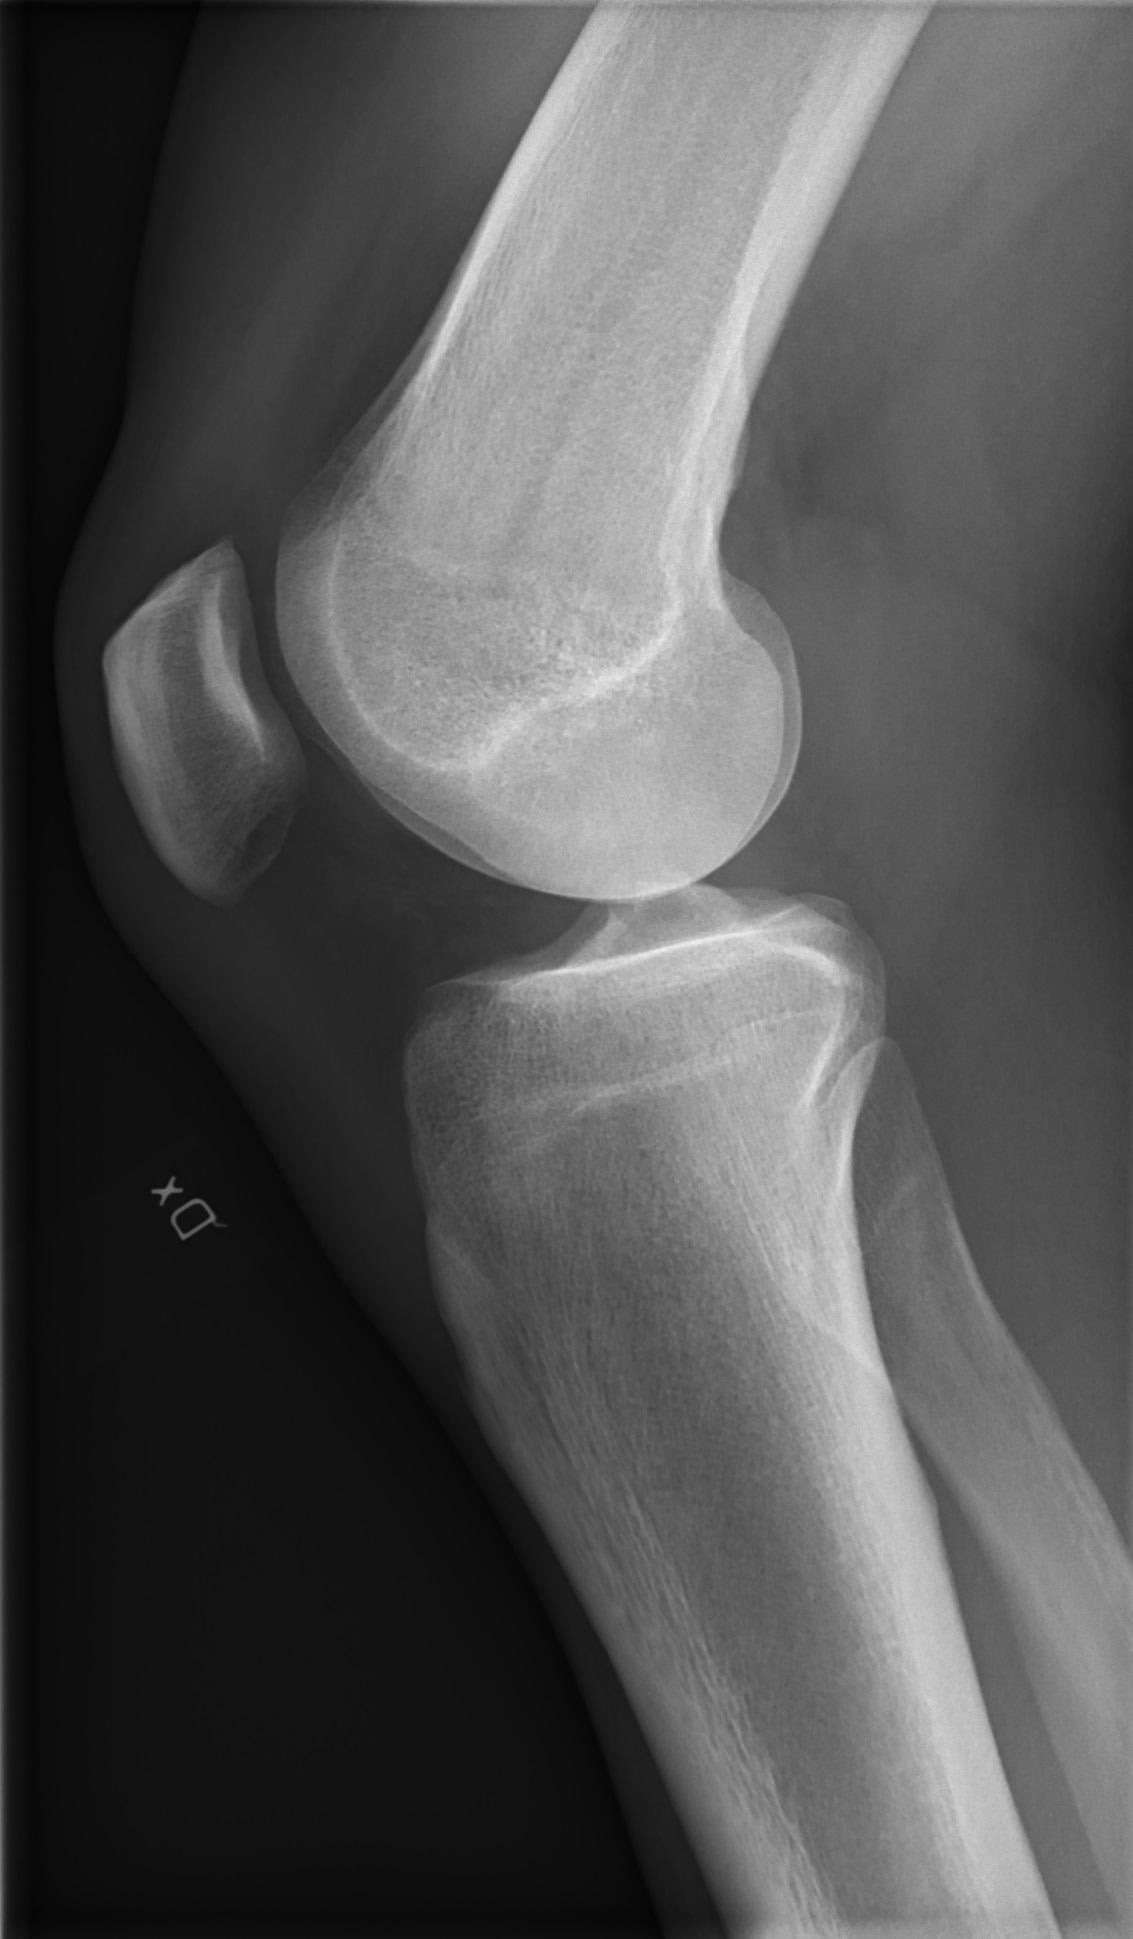

膝蓋內的小零件損傷X光是看不出來,磁力共振掃描可以看得一清二楚。

王稚暉醫生提醒,像該患者的小小車禍,看似骨頭都沒問題,膝蓋內的「小零件」或許已受損,小零件損傷X光是看不出來,磁力共振掃描可以看得一清二楚,還好目前已有膝蓋軟骨移植技術,對膝蓋軟骨受傷或退化性膝關節炎的病患多了一項醫療選擇,不過,膝蓋軟骨移植對50歲以下的患者、單一破損傷口者成功率相對較高。